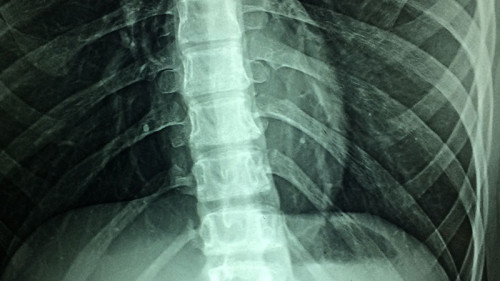

Sogenannte Hybrid Assistive Limbs (HAL®) sind Roboteranzüge und kommen in der Rehabilitation von Patienten mit Rückenmarkverletzungen zum Einsatz. Sie unterstützen Bewegungen wie Aufstehen, Gehen und Hinsetzen.

Dabei ist HAL der weltweit erste nervengesteuerte Roboteranzug, bei dem das Gehirn die Steuerung der Gehbewegungen neu erlernen kann. Es analysiert und verarbeitet die nerveninduzierten Impulse des Patienten.

Die vom Gehirn gesendeten Signale werden mittels Elektroden an der Hautoberfläche aufgenommen, in Bewegungsbefehle umgesetzt und an die Elektromotoren im Hüft- und Kniebereich weitergeleitet. Das Gehirn lernt dadurch, sein Bewegungsschema zu reorganisieren. Die Roboter-Bewegungen werden somit vom Patienten aktiv gesteuert und durch HAL® unterstützt und verstärkt. HAL® ist der erste Roboteranzug, der in Japan, der EU, den USA und weiteren Ländern eine Sicherheitszertifizierung erhielt.

Entscheidende Voraussetzung für ein solches Training sind noch vorhandene Restfunktionen in der Beinmuskulatur.